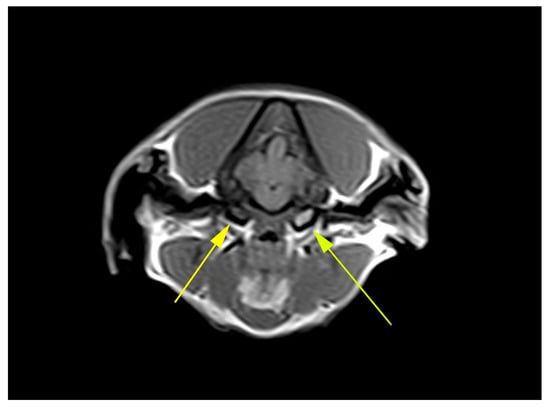

There was no statistically significant difference for breed and sex (p = 0.32) or breed and age (p = 0.318), meaning that sex and age were comparable for all breeds. However, there was a statistically significant difference for all breeds for CM (p < 0.001), SM (p = 0.003) and syrinx size (p = 0.003), meaning that CM1/CM2 and SM+ were present at a significantly higher rate in all breeds. CM was seen the most in the Chihuahua (75%), Griffon (96%), Maltese (83%), Pug (75%) and Yorkshire terrier (80%) breeds. CM and/or SM were only seen in one out of nine Dachshunds. SM was observed in all breeds, with the highest frequency in the Griffon (89%), French Bulldog (70%) and Chihuahua (62%). Only in the French Bulldog was there evidence of a high number of dogs being affected by SM and not CM. In all other breeds, CM and SM appeared to predominantly occur simultaneously (Table 2). In all breeds, SM was observed with an average syrinx size of 2.9 ± 2.4 mm (Mean ± SD), with the French Bulldog, Pug, Griffon and Chihuahua having larger syrinxes (Table 2). MEE was only seen in the French Bulldog, two Chihuahuas and four crosses. Figure 1 and Figure 2 are examples of two of the collected MRI images.

Figure 2.

Example of a T1-weighted MRI of a 3-year-old King Charles Spaniel. Yellow arrows—MEE. Taken with a 0.4 T MRI scanner.